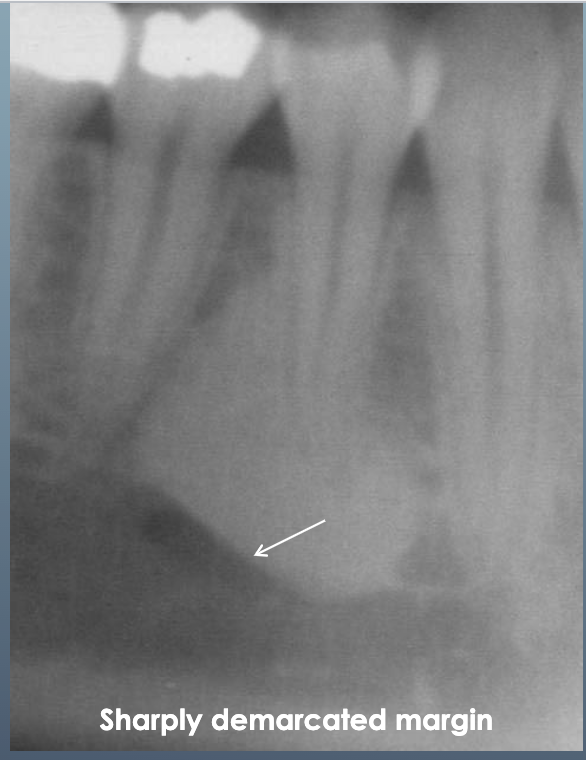

13

What’s ths?

IDIOPATHIC OSTEOSCLEROSIS